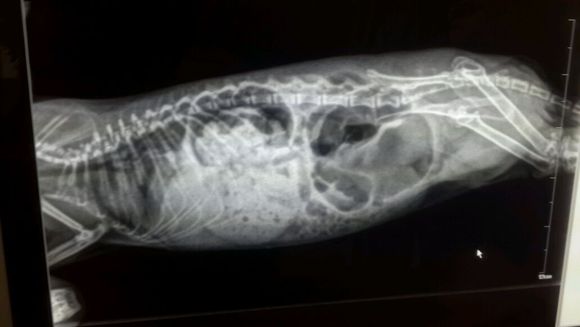

此时首先需要去专业可以给龙猫治病的宠物医院拍片,判断肠梗阻程度,再根据程度进行处理。